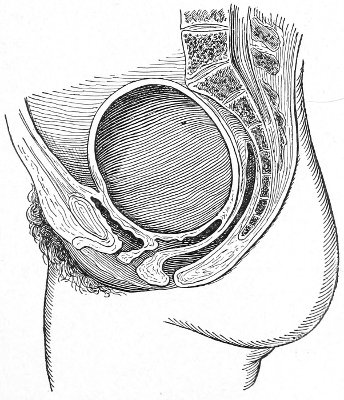

The symptoms of this condition are due to retention of the uterine discharges. There is no discharge of 53 menstrual blood from the vagina. Attacks of pain occur periodically at the menstrual periods. A cystic tumor, which may be felt by rectal examination, is present. The tumor consists of the distended portion of the vaginal canal (hematocolpos), and sometimes of the distended cervical canal and body of the uterus. The contents of the hematocolpos are usually sterile, although they may become purulent (pyocolpos).

The diagnosis is readily made by vaginal and rectal examination.

Treatment consists in incision and excision of the vaginal septum and the suture of the vaginal mucous membrane above to that below the obstruction. In very severe cases it is difficult to maintain the patulous condition of the vaginal canal on account of subsequent cicatricial contraction. In such cases the repeated passage of vaginal bougies or the transplantation of mucous membrane has been resorted to.